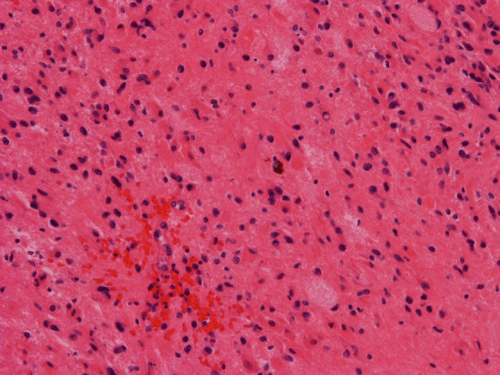

Clinical informationThe patient was a 20 year-old woman who was about 5 weeks postpartum. She presented with nausea, vomiting, and severe headache. MRI scan revealed a large cystic right ventricular tumor with extension to the right parietal occipital area but the main bulk of the tumor is within the lateral ventricle. The cystic component, however, extends to the cortical rim of the parietal occipital cortical region. Some calcifications are present. The differential diagnosis include choroid plexus tumor and intra-axial glial neoplasm. The tumor was resected and the following images are representative of the tumor.

Pathology of the Case: MRI shows a large mass with the more solid component located in the lateral ventricles and the cystic component protruding into the cortical area. The solid area is enhanced (Panel A). On low magnification, the lesion has alternating area of high and low cellularity (Panel B) with scattered calcifications in some of the sections. Medium and high magnification demonstrates perivascular coronary arrangement of cytoplasmic processes (Panel C, D, and E). The nuclei are bland and mitotic figures are not readily seen. Randomly scattered brown pigment containing cells are found in multiple areas of the tumor (Panel F, G, and H). Scant lipidized cells with enlarged nuclei (Panel I) are also present. The tumor cells are strongly positive for glial fibrillary acidic protein (GFAP) (Panel J and K) and S100 protein but are negative for epithelial membrane antigen (EMA), neurofilament proteins, and NeuN. The overall Ki67 labeling is low but focal small areas (about the size of one high power field) has increased labeling. The pigment appears to be melanin on microscopic examination. These pigments are positive with Fontana-Masson stain (Panel L) but negative for Prussian blue stain for iron (Panel M). These features confirmed that these are melanin pigments. The pigment granules are positive for periodic acid-Schiff reaction (N), negative for Ziehl-Neelsen (acid fast) stain..

DIAGNOSIS: Ependymoma, WHO grade II, pigmented.